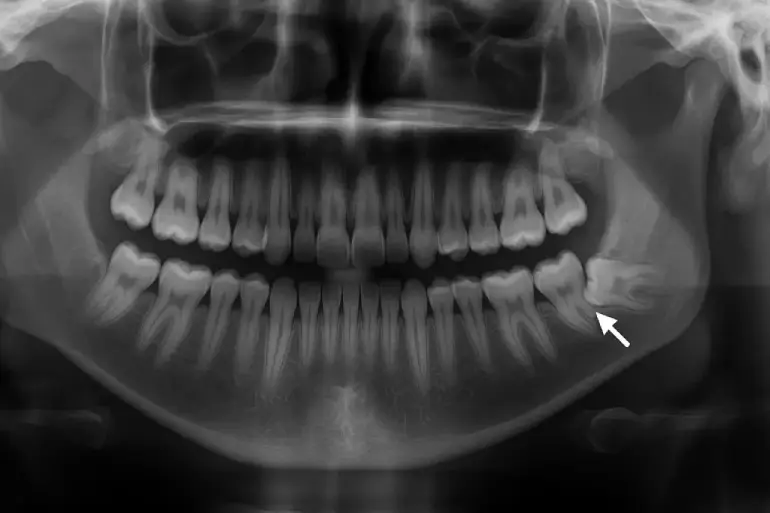

Ortopantomogram (ortopan) je zlatni standard za dijagnozu impaktiranih umnjaka. Ovaj snimak daje pregled cele gornje i donje vilice na jednom filmu.

Na njemu lekar jasno vidi tačan položaj svakog impaktiranog zuba, njegovu orijentaciju (da li raste ukoso, horizontalno ili vertikalno), oblik i broj korenova, kao i njihov odnos sa okolnim vitalnim strukturama.

Posebno je važan odnos između korena donjeg umnjaka i donjeg alveolarnog nerva.

Ovaj nerv inerviše usnu, bradu i deo desni. Ukoliko snimak pokaže da koren umnjaka prodire u kanal ili ga preklapa, hirurg mora da bude izuzetno oprezan prilikom vađenja.